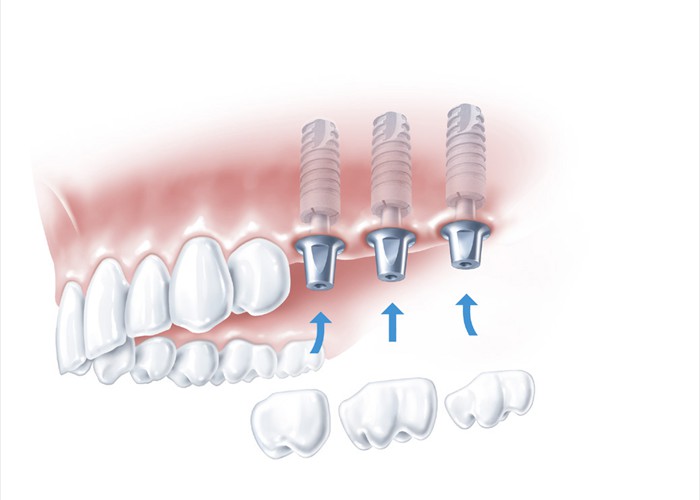

Aufsetzen der Kronen auf die Implantate

Aufsetzen der Kronen auf die Implantate